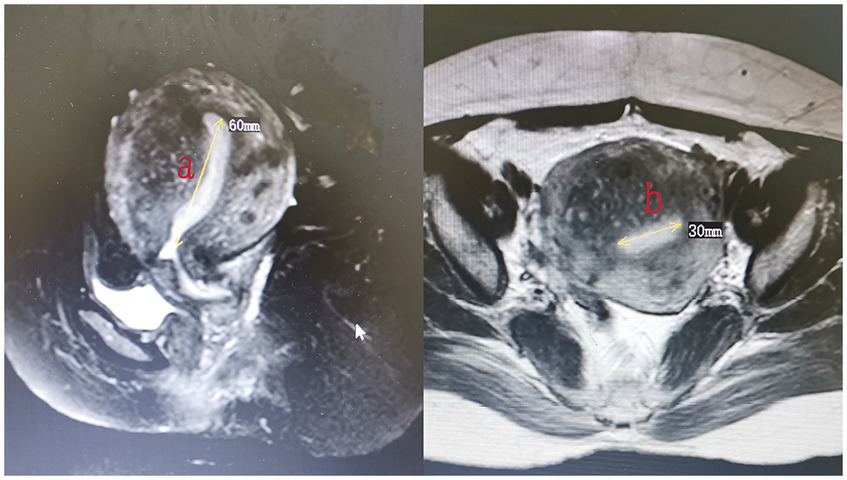

All patients underwent MRI within 3 days after HIFU to define the condition of the endometrium and evaluate the non-perfused volume (NPV). The volume of adenomyotic lesions and NPV were measured using the following equation for the prolate ellipsoid (7): volume = 0.5233 × a × b × c (a, b, and c are the longitudinal, anteroposterior, and transverse dimensions, respectively). The volume of adenomyotic lesions was defined as the volume of the part of the uterus where the focal adenomyotic lesions were located (Figure 1). The volume of the ablation lesions was defined as the volume of the non-perfused area (Figure 2). The NPV ratio (NPVR) was defined as the NPV divided by the lesion volume, NPVR = NPV/volume of the adenomyotic lesion × 100%. Successful treatment with HIFU was defined as an NPV of ≥1 cm3 in the planned ablation zone (8).

Figure 2

The measurement of the volume of the destroyed lesions (volume = 0.5233 × a × b × c).